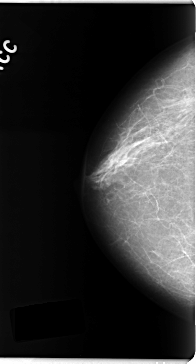

C_0185_1.RIGHT_MLO

RIGHT_CC LINES 4720 PIXELS_PER_LINE 2544 BITS_PER_PIXEL 12 RESOLUTION 50 NON_OVERLAY

RIGHT_MLO LINES 4752 PIXELS_PER_LINE 2528 BITS_PER_PIXEL 12 RESOLUTION 50 NON_OVERLAY